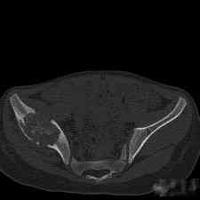

女, 16 岁, 左髂部疼痛,软组织肿块

女, 16 岁, 左髂部疼痛,软组织肿块数月,髋关节活动受限。 左髂骨溶骨性破坏,伴有巨大软组织肿块,病灶累及髋臼。考虑骨肉瘤可能大。...